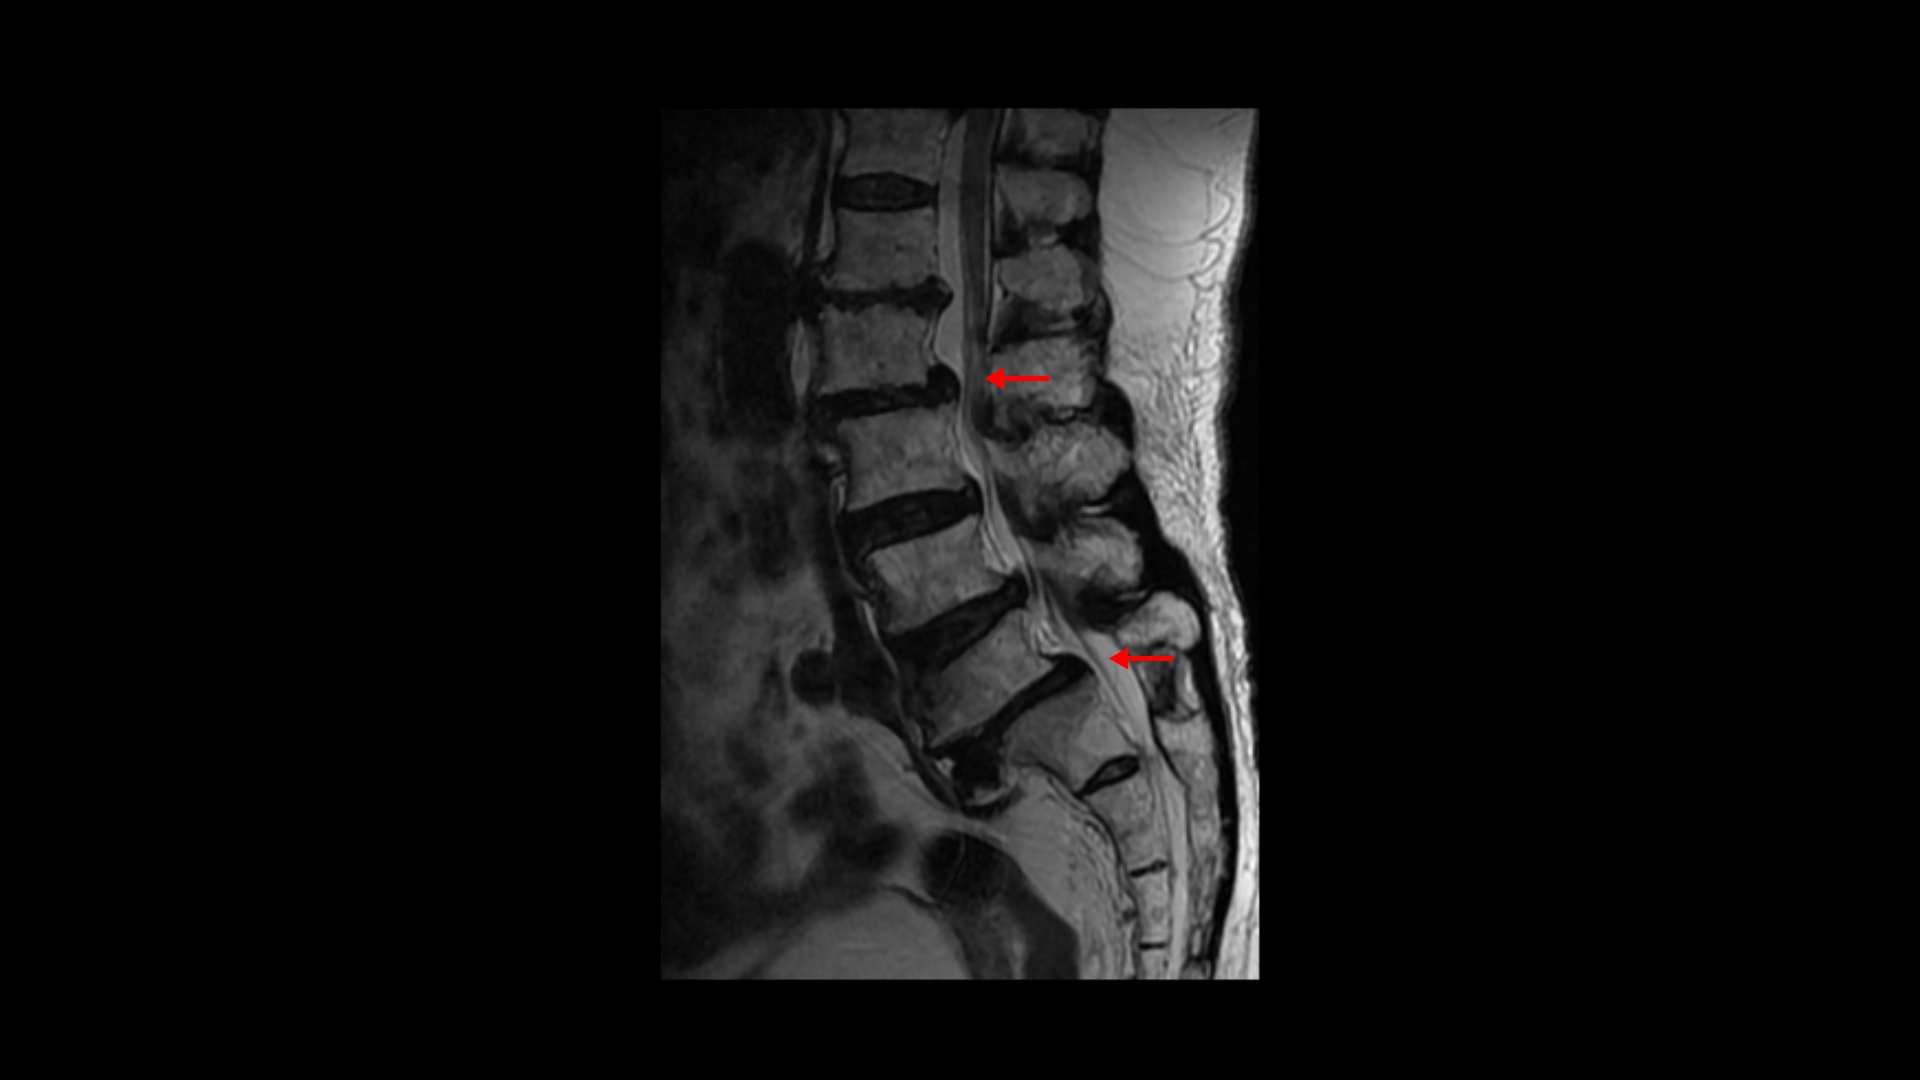

이분 MRI를 보면 보시다시피 허리의 5마디가 전부 퇴행이 진행되어 있습니다.

우선 전방전위가 2마디에 있고

여러 마디 2번 3번, 4번 5번에 척추관협착이 있고

2번 3번, 4번 5번, 오른쪽 신경가지가 빠져나가는 구멍들이 다섯 마디 전부가 다 오른쪽 좁아져 있습니다.

이분의 오른쪽 엉치와 다리가 저리고 아픈 원인은 이것 때문인 걸로 보입니다.

그런데 이분은 허리도 굽으셨는데 척추근육, 특히 허리를 세워주는 기립근을 mri에서 보면 허리 다섯 마디 전체에서 기립근의 근육이 지방으로 변해서 하얗게 보이는 지방화가 심합니다.

이렇게 근육이 지방으로 심하게 변하고 기능이 떨어지면 허리를 펴기가 어렵고 허리가 아플 수 밖에 없습니다. 여기 건강한 기립근과 비교해서 보면 그 차이를 금방 알 수가 있습니다. 기립근 크기도 차이가 크고 하얗게 지방으로 변해버린 부분을 잘 보실 수 있습니다.